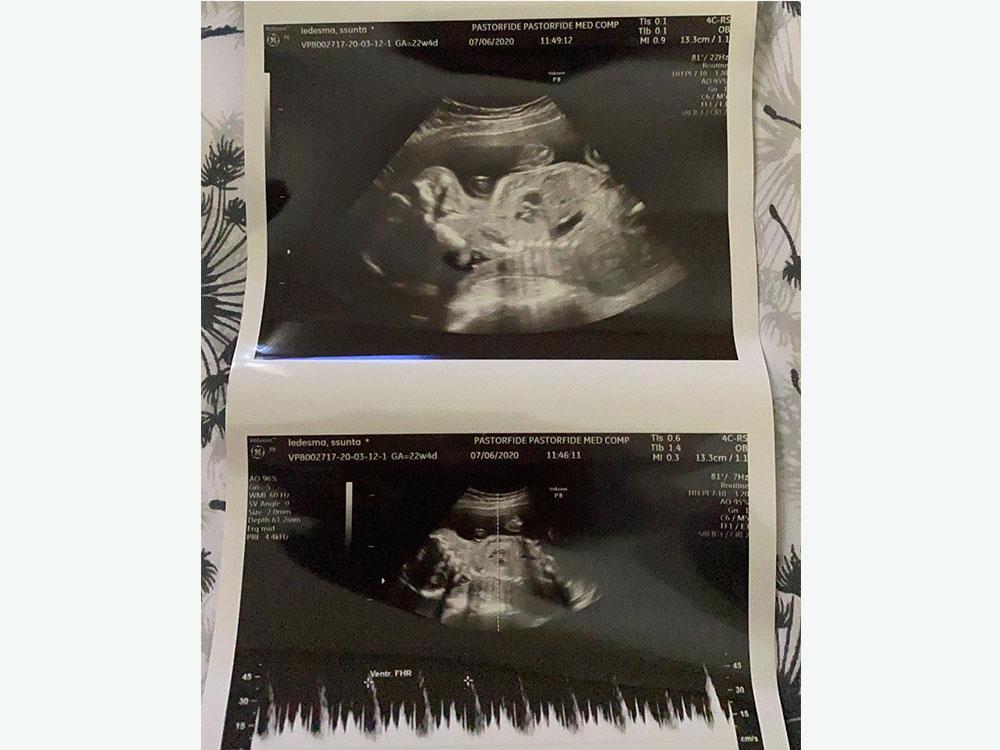

Ultrasound